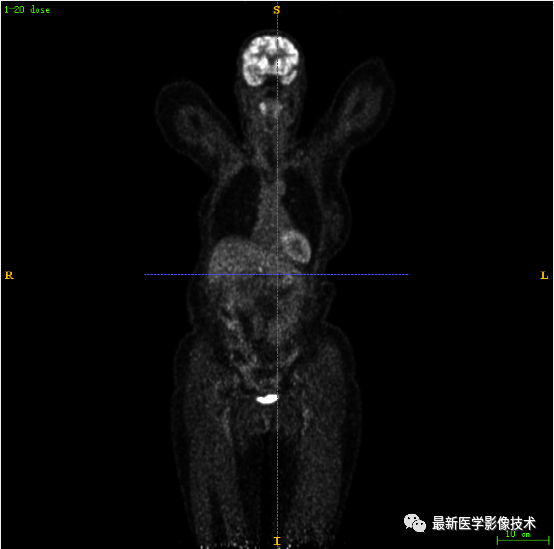

7.1、低剂量2重建结果

第一张是低剂量2的PET图像,第二张是full剂量PET图像,第三张是网络重建的PET图像。